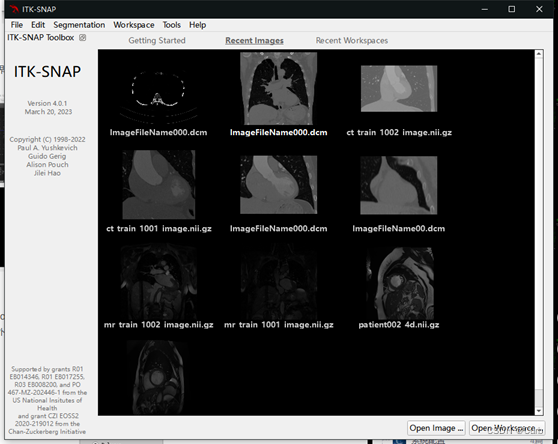

标注软件:ITK-SNAP

1 初始界面